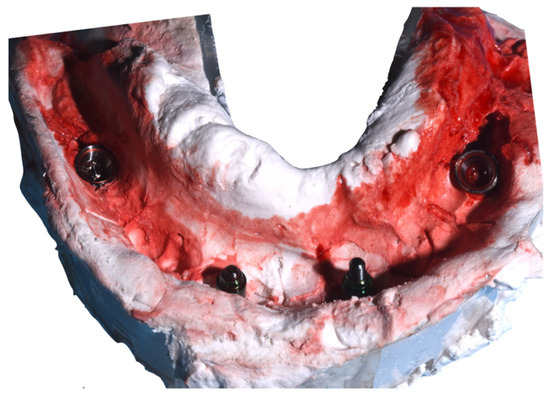

2. Case Report

Surgery Appointment